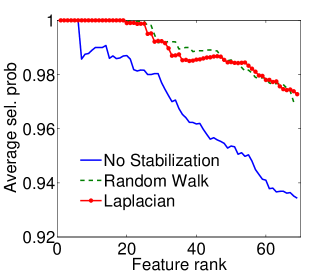

|

|

| (a) Cumulative, | (b) Stagewise (Shared), |

|

|

| (c) Stagewise (Separate), | (d) Stagewise (Separate), |

We now examine the models stability against data sampling and evaluate the stabilizing property of the proposed method (Sec. 6.2). For each fold, we generated samples, each of which was drawn randomly from % of training data. Each example resulted in a model, and the feature weights were recorded and finally the results of all folds – models – were combined. Figs. 5(a–d) show the indices (Eq. (5)) as functions of the rank list size , for all ordinal classifiers. The instability is clearly an issue – the average selected probability drops as more features are included. Using both the Laplacian and random walk regularization methods (Eqs. (9,10)), the improvement in stability is evidenced in all settings. The instability and stabilizing effect were similarly obtained with the indices (Figs. 6(a–d)).

|

|

| (a) Cumulative, | (b) Stagewise (Shared), |

|

|

| (c) Stagewise (Separate), | (d) Stagewise (Separate), |